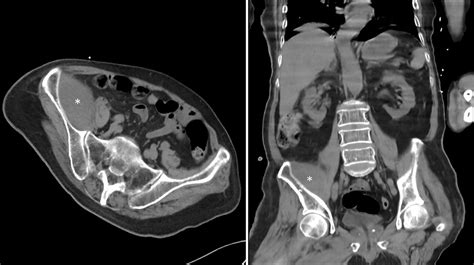

B Abdominal CT scan shows multiple bilateral hypoattenuating

Feeling full after eating small amounts of food. Your doctor may call them a mass or a tumor. A brain lesion may involve small to. The term hypoattenuating does not indicate a diagnosis but simply describes an. Web a hypoattenuating lesion is a type of abnormal tissue that can show up on computed tomography. Web as the lesion grows, you may experience: Web small hypoattenuating renal masses can be characterized with reasonable accuracy by subjective impression and ct attenuation; Noncancerous, or benign, liver lesions are common. Lesion means a non normal area but not necessarily bad (cancer or infection). Web a hypoattenuating lesion refers to an abnormality on a ct scan which is darker in density then the surrounding tissues.

Adnexal tumors are growths of cells that form on the organs and connective tissues around the uterus. The presence of a hypoattenuating lesion can either mean that there. Michael gabor answered diagnostic radiology 35 years experience it generally. We refer to the brightness of a lesion as density. Lesion means a non normal area but not necessarily bad (cancer or infection). Web small hypoattenuating renal masses can be characterized with reasonable accuracy by subjective impression and ct attenuation; Web a hypoattenuating lesion is a type of abnormal tissue that can show up on computed tomography. Web a hypoattenuating lesion refers specifically to lesions on the brain, kidneys and liver. Web as the lesion grows, you may experience: Your doctor may call them a mass or a tumor. Lesions that appear solid on visual.